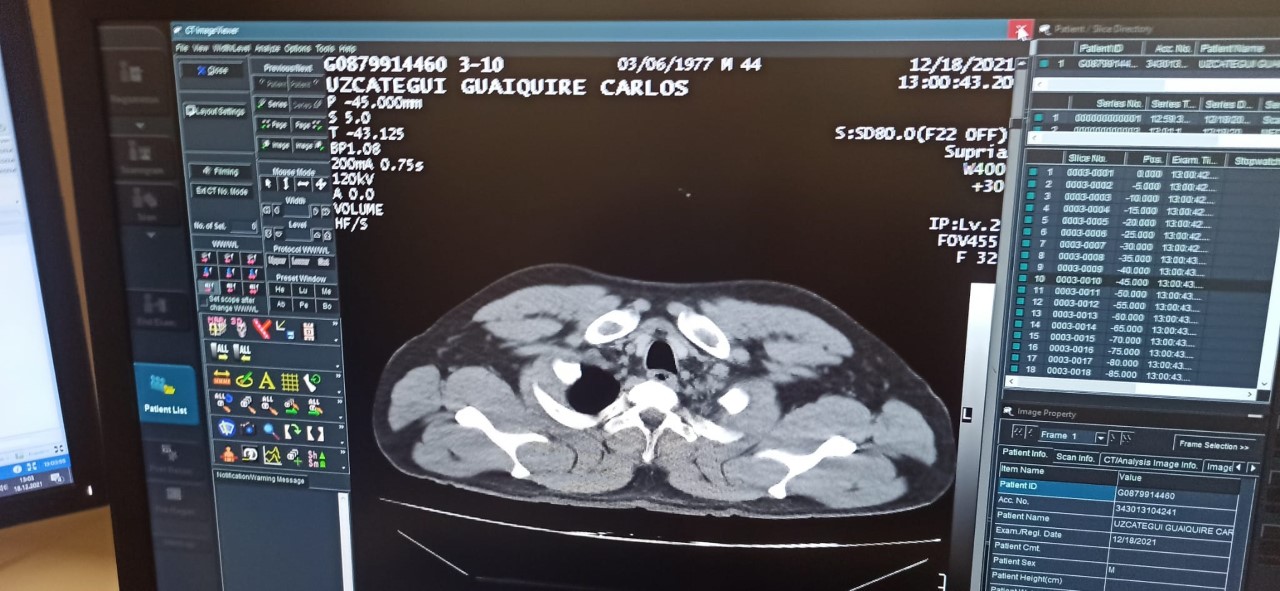

C.M.U.G’un hastanede yapılan tomografi kontrolünde mide ve bağırsaklarında 12 adet kapsül kokain tespit edilmesini üzerine, ameliyata alındı. C.M.U.G., tedavi gördüğü hastaneden taburcu edildikten sonra Cumhuriyet Savcılığı’na sevk edildi.